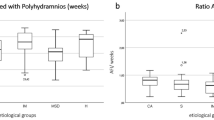

In addition, live-born children with malformations were significantly more often preterm than children without additional abnormalities (p > 0.001) (shown in Fig. 3).